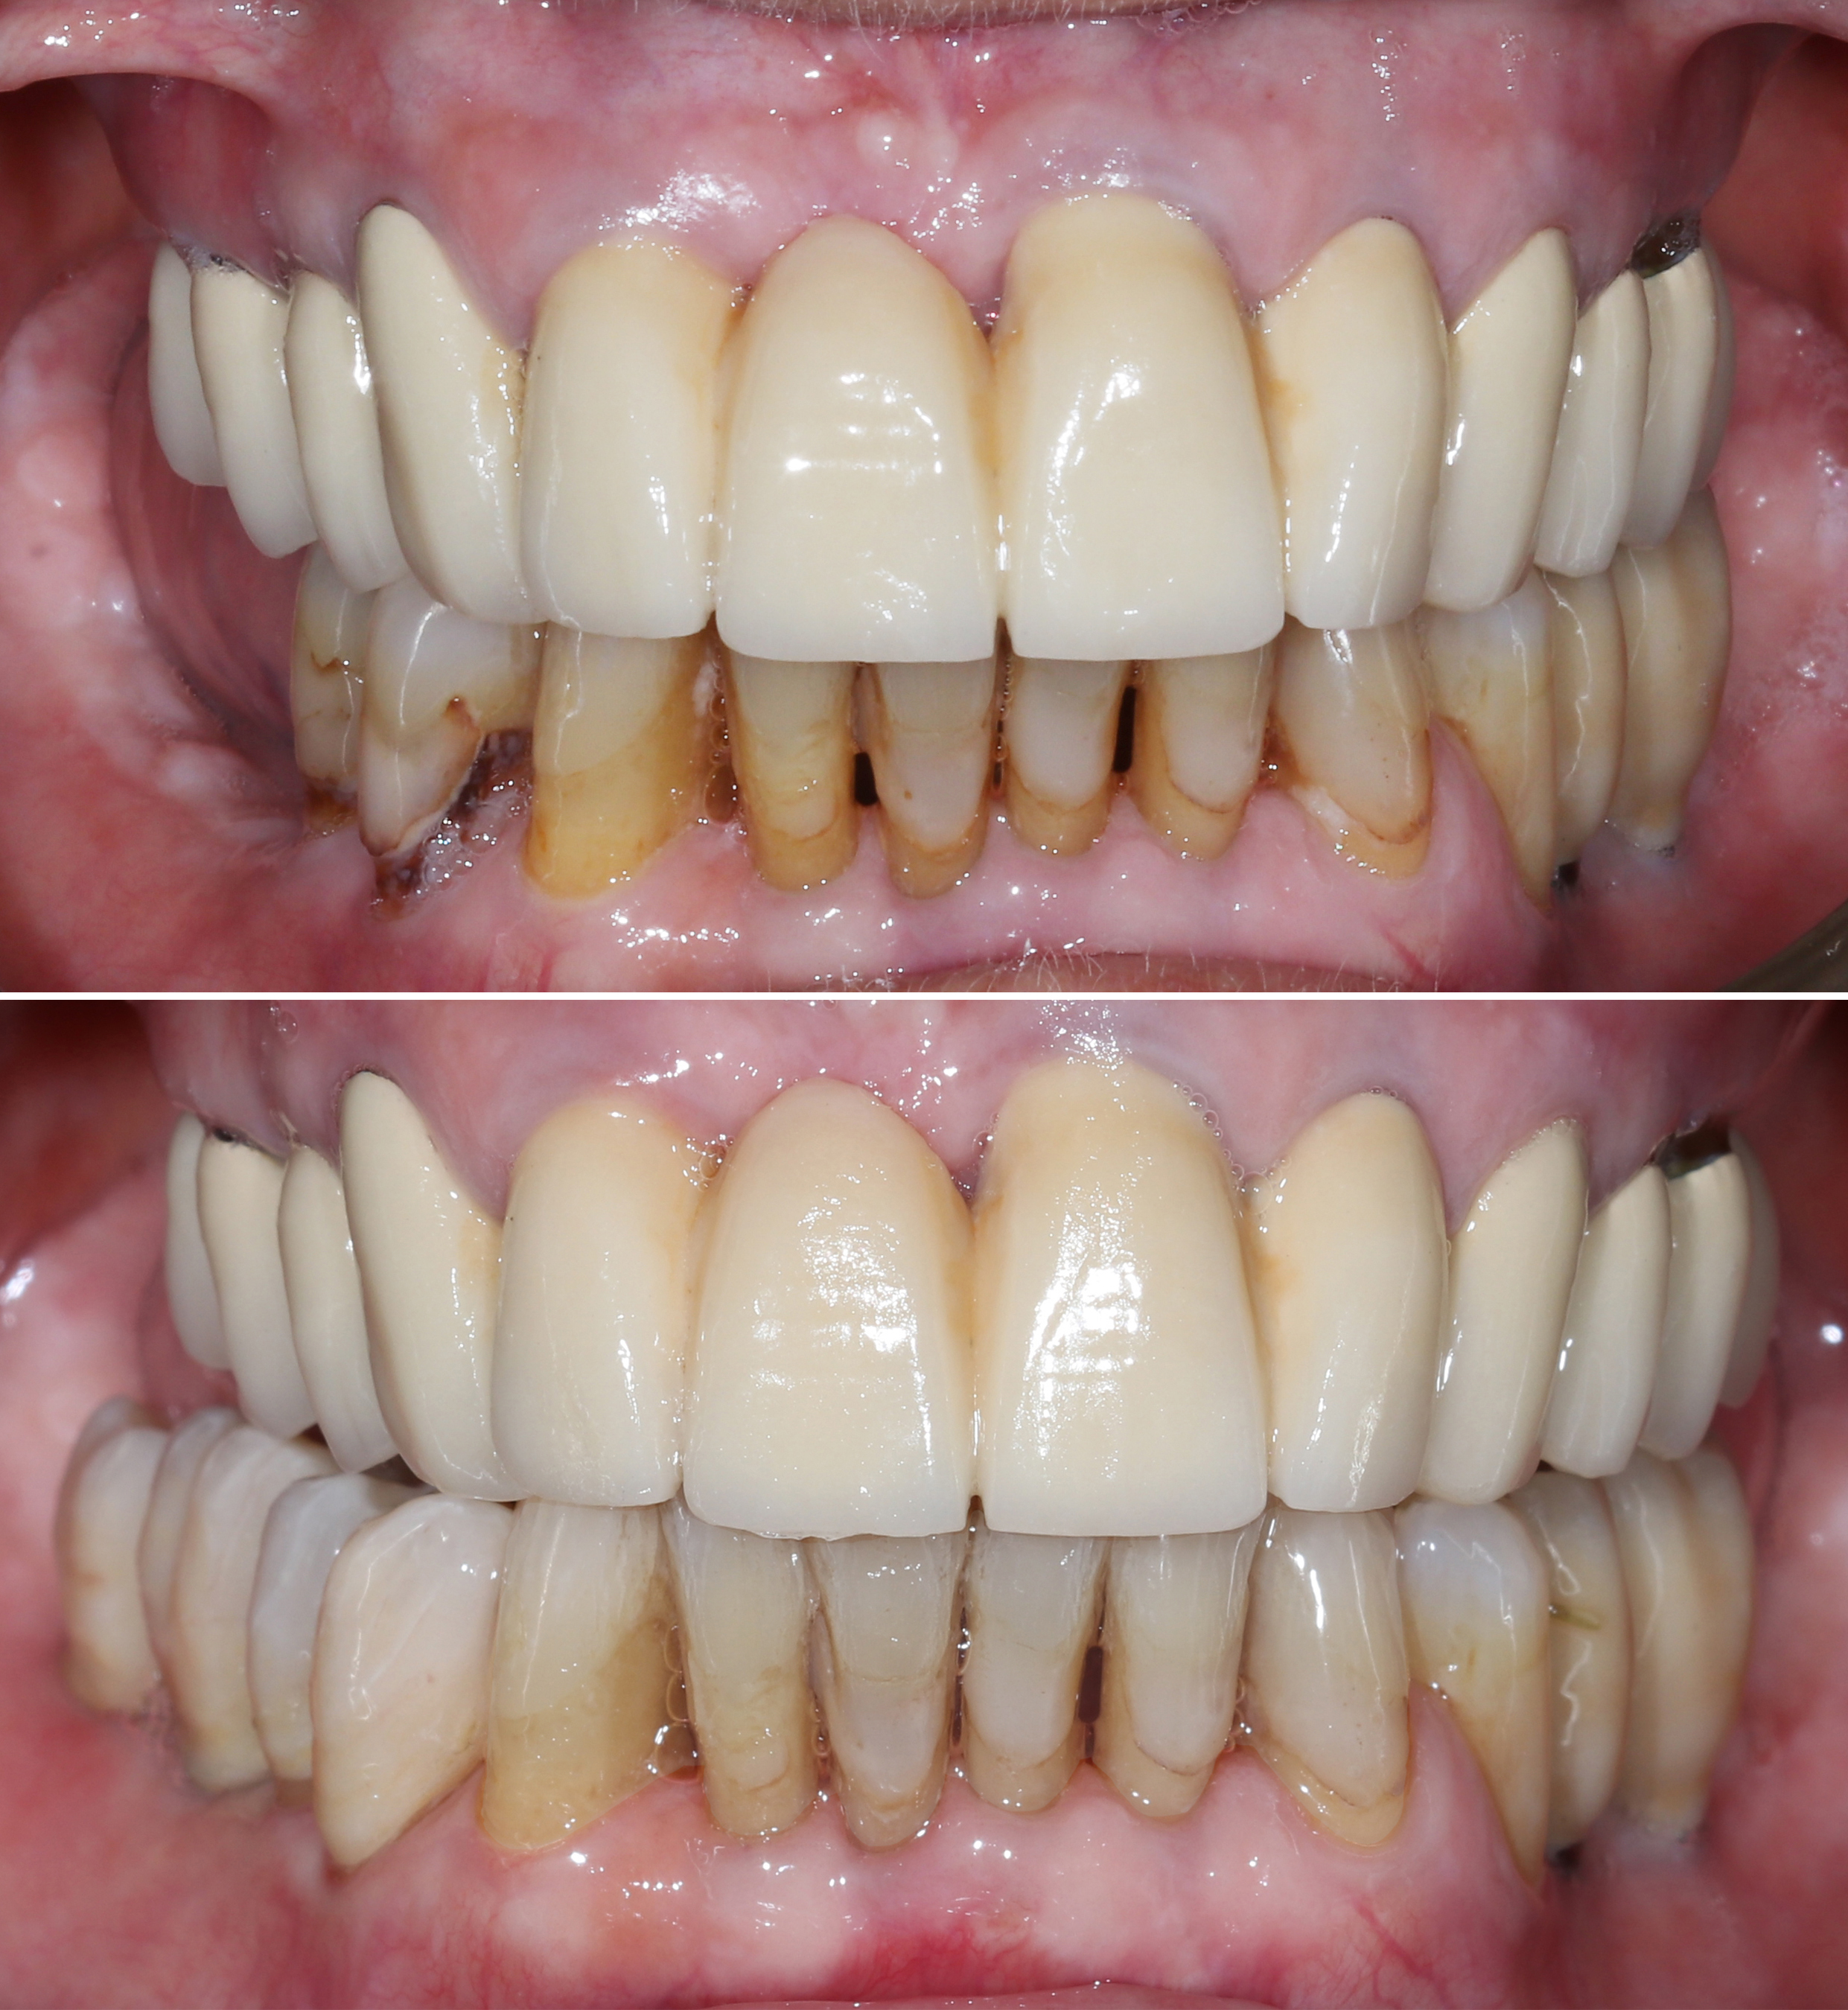

Αρχική κατάσταση - Χαμόγελο και πρόσθια άποψη

Αρχική κατάσταση - Πλάγια άποψη